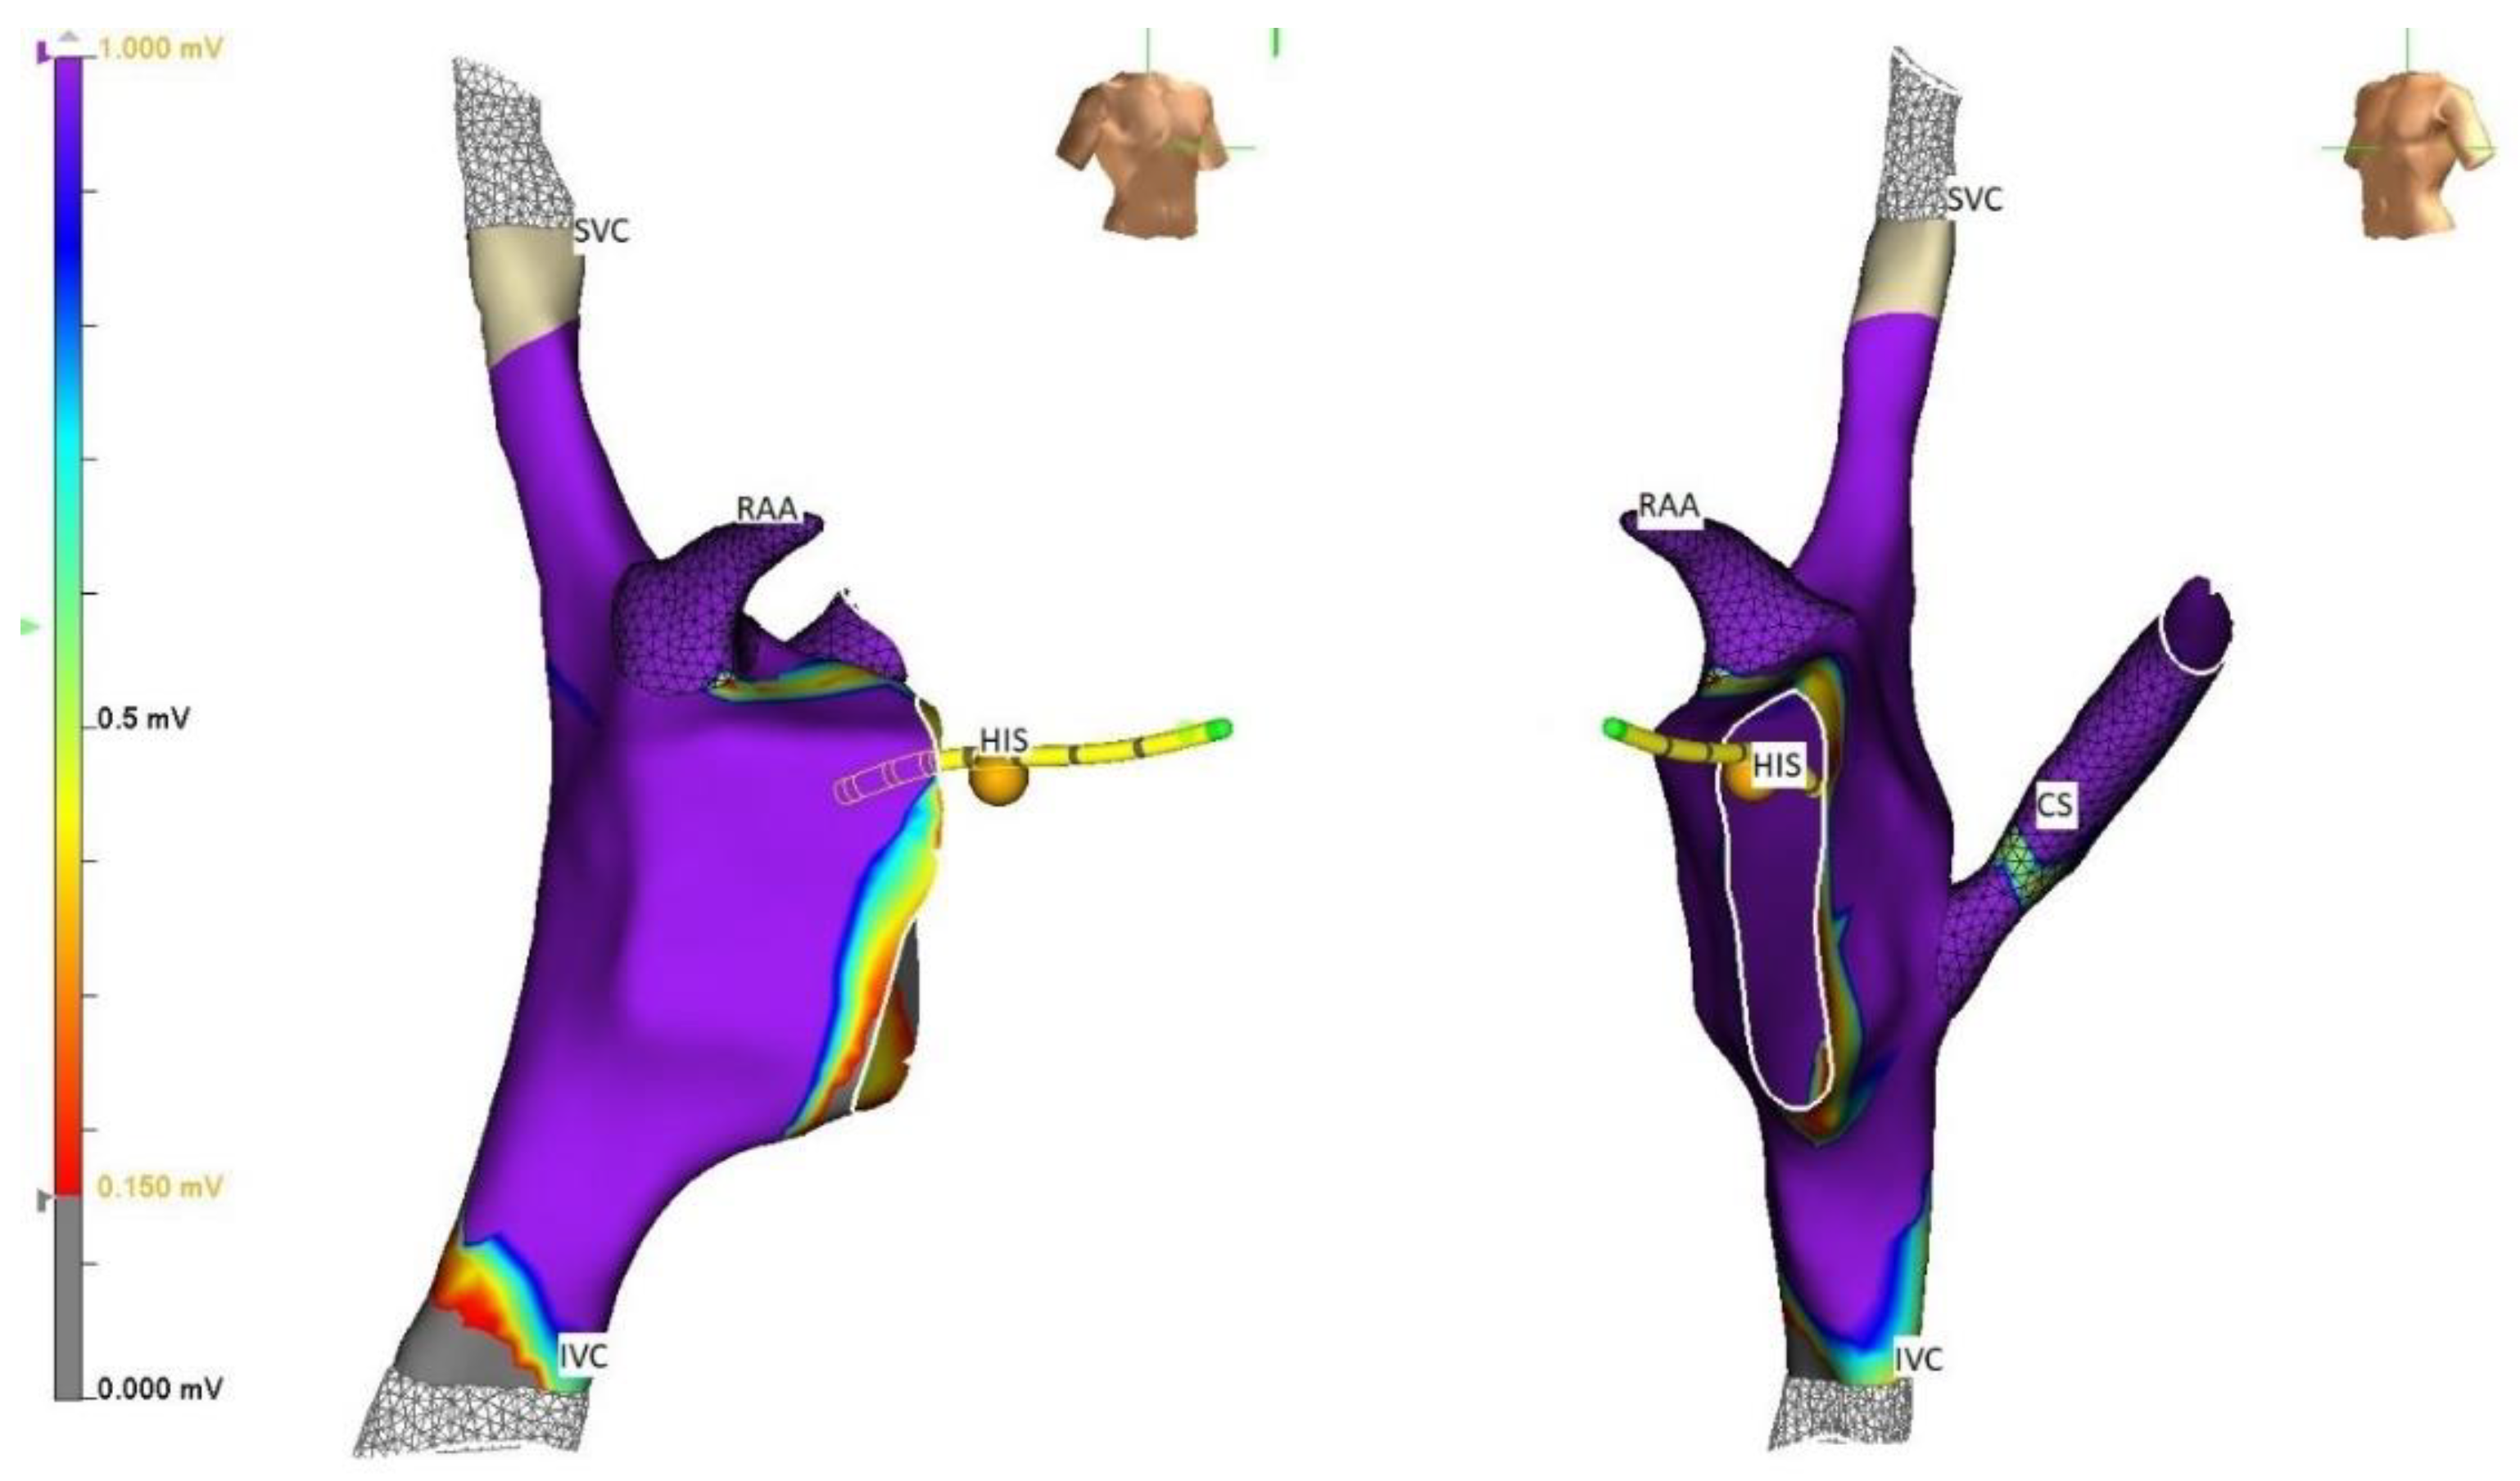

4. Strategies

5. Techniques